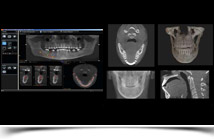

Nos permite la exploración detallada de los huesos maxilares y su relación con las estructuras faciales. Se utilizan en implantología oral, ortodoncia y cirugía para realizar diagnósticos y estudios detallados así como proyecciones radiográficas de todo el cráneo en una única imagen digital.